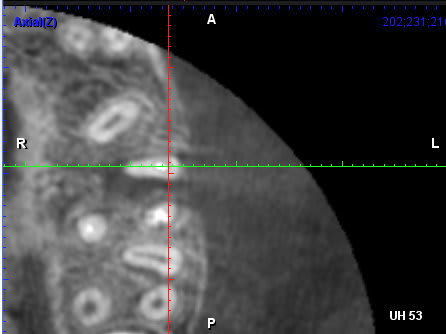

Une jeune fille de 14 m'a été adressée pour retraiter la 26 donc la fistule V ne disparait pas.

Elle n'a pas mal et le sondage ne montre pas de poche >2mm

Sur le CBCT une belle LIPOe avec plus de corticale en V.En DIU d'endo j'ai appris "pas de corticale depuis le collet => avulsion. Puis en bouquinant un peu de cases reports, j'ai tenté des cas similaire et un Retraitement orthograde avec une séance d'hydroxyde ont fait disparaitre la fistule. Les lesions dimunuent petit à petit (j'ai pas assez de recul encore)

il faudrait d'autres images CBCT et ta mire est en

plein sur la zone à étudier;si on regarde la 27

on devine un canal vestibulaire très allongé avec mise en commun mv1 mv2

Suspicion d'un mv2 sur 26;les séances à l'hydroxyde de calcium

Et il y a bien un MV2 qui se reunit avec le MV1 ds le 13/ apical et a en plus une sortie propre.

Ok, donc 2 autres coupes axiales:

Mais au bout d'un moment la 3 d montre pas tout: tu peux ne pas voir une lumiere canalaire qui existe dans la dent.

+ l'artefact du gros cone de gutta

ton canal mésio ves avec commnunication MV1 MV2 est de forme

allongée comme sur la 27 et ton cône de gutta est central

et n'obture pas tout l'apex de façon hermétique (par contre

tout ceci ce sont des interprétations et je pense que le bout de l'apex mésio ves de ta 26 est allongé ;c'est pourquoi on réclame plus de coupes CBCT possible puisque tous les mm et en particulier la coupe du bout des 3 apexs

de ta 26

je pense que la LIPOE vient de la racine mésiale;